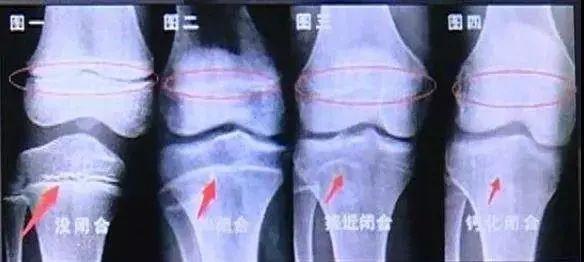

骨龄超过实际年龄1年以上。我们称为骨龄超前。

骨龄小于实际年龄1年以上,我们称为骨龄延迟(或者骨龄落后)。

骨龄评估的准确性和成年身高预测非常相关。目前医院常用的骨龄评估的方法主要是G-P骨龄图谱法和软件辅助评定骨龄。简单的说骨龄图谱法是根据各年龄段骨成熟的标志,以及对比干骨后端融合过程来判断骨龄(大部分医院采用)。